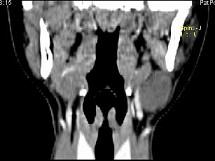

问题 女,16岁,发现左颈部肿块两年,CT如图所示,最可能的诊断为 ( )

选项 A、左侧鳃裂囊肿 B、囊性转移癌 C、咽部神经鞘瘤 D、咽旁脓肿 E、囊状水瘤

答案 A